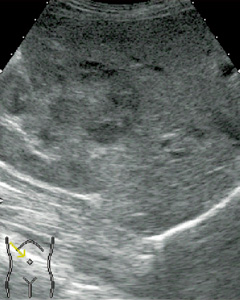

■ Flash機能とMicrobubble Trace Imaging(MTI)(図3)

体内に貯まったソナゾイドは,高音圧送信することで破壊することができる。

Flash機能は高音圧送信でソナゾイドを破壊し,再環流を観察する機能である。また,MTIは,造影剤による高輝度部を重ね合わせる画像で,血管像の観察に適している。

図3 HCCのMTI像 (画像ご提供:三重大学 田中秀明先生)

a:MTI像

b:LowMIでのFundamental像